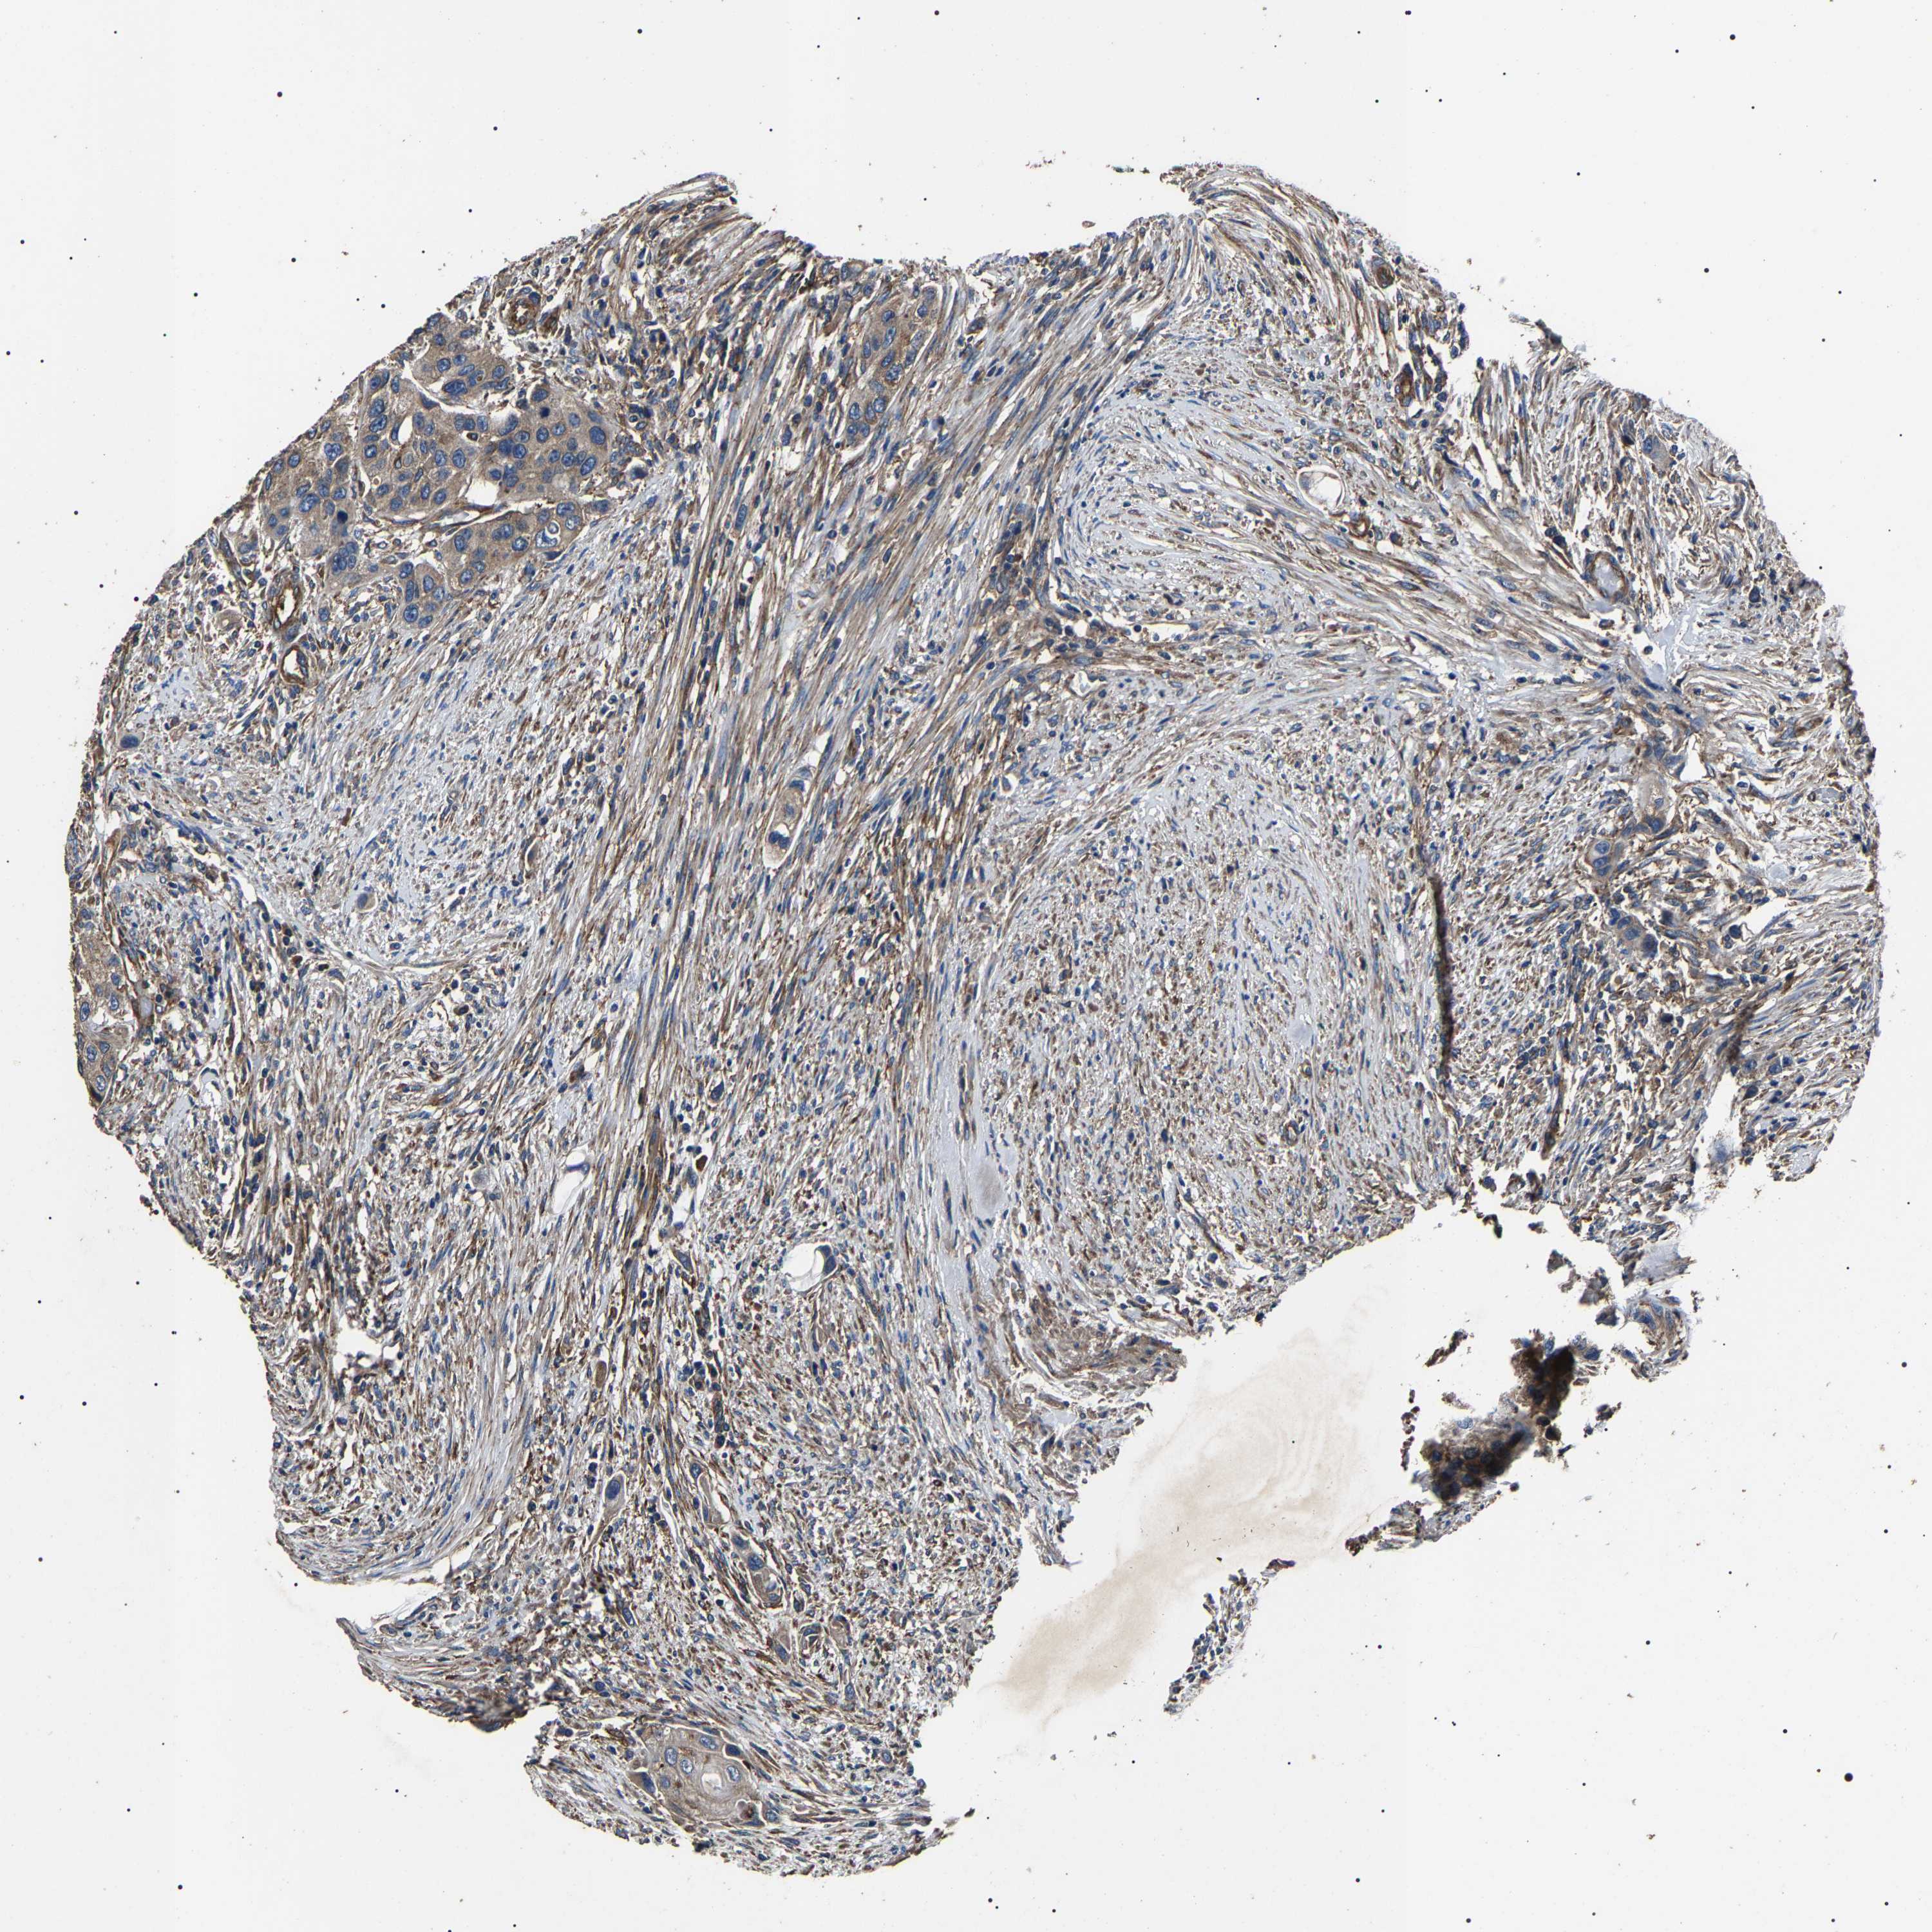

UROTHELIAL CANCER - Protein expressioni

A mouse-over function shows sample information and annotation data. Click on an image to view it in a full screen mode. Samples can be filtered based on level of antibody staining by selecting one or several of the following categories: high, medium, low and not detected. The assay and annotation is described here.

Antibody stainingi

Antibody staining in the annotated cell types in the current human tissue is reported as not detected, low, medium, or high, based on conventional immunohistochemistry profiling in selected tissues. This score is based on the combination of the staining intensity and fraction of stained cells.

Each image is clickable and will lead to virtual microscopy that enables deeper exploration of all samples and also displays staining intensity scores, fraction scores and subcellular localization as well as patient and tissue information for each sample.

Antibody HPA018447

Staining

High

Medium

Low

Not detected

Intensity

Strong

Moderate

Weak

Negative

Quantity

>75%

75%-25%

<25%

None

Location

Nuclear

Cytoplasmic/membranous

Cytoplasmic/membranous,nuclear

Urothelial carcinoma, Low grade

Urothelial carcinoma, High grade